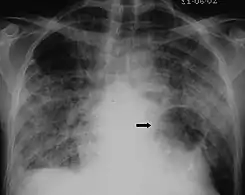

The diagnosis can be confirmed by the characteristic appearance of the chest X-ray and an arterial oxygen level (PaO2) that is strikingly lower than would be expected from symptoms. Gallium 67 scans are also useful in the diagnosis. They are abnormal in about 90% of cases and are often positive before the chest X-ray becomes abnormal. Chest X-ray typically shows widespread pulmonary infiltrates. CT scan may show pulmonary cysts (not to be confused with the cyst-forms of the pathogen).

X-ray of a cyst in pneumocystis pneumonia[7]

High-resolution computed tomography (HRCT) showing ground-glass attenuation with a geographic or mosaic distribution.[7]

HRCT of cysts of pneumocystis pneumonia. These are usually multiple and bilateral, but range in size, shape and distribution.[7]